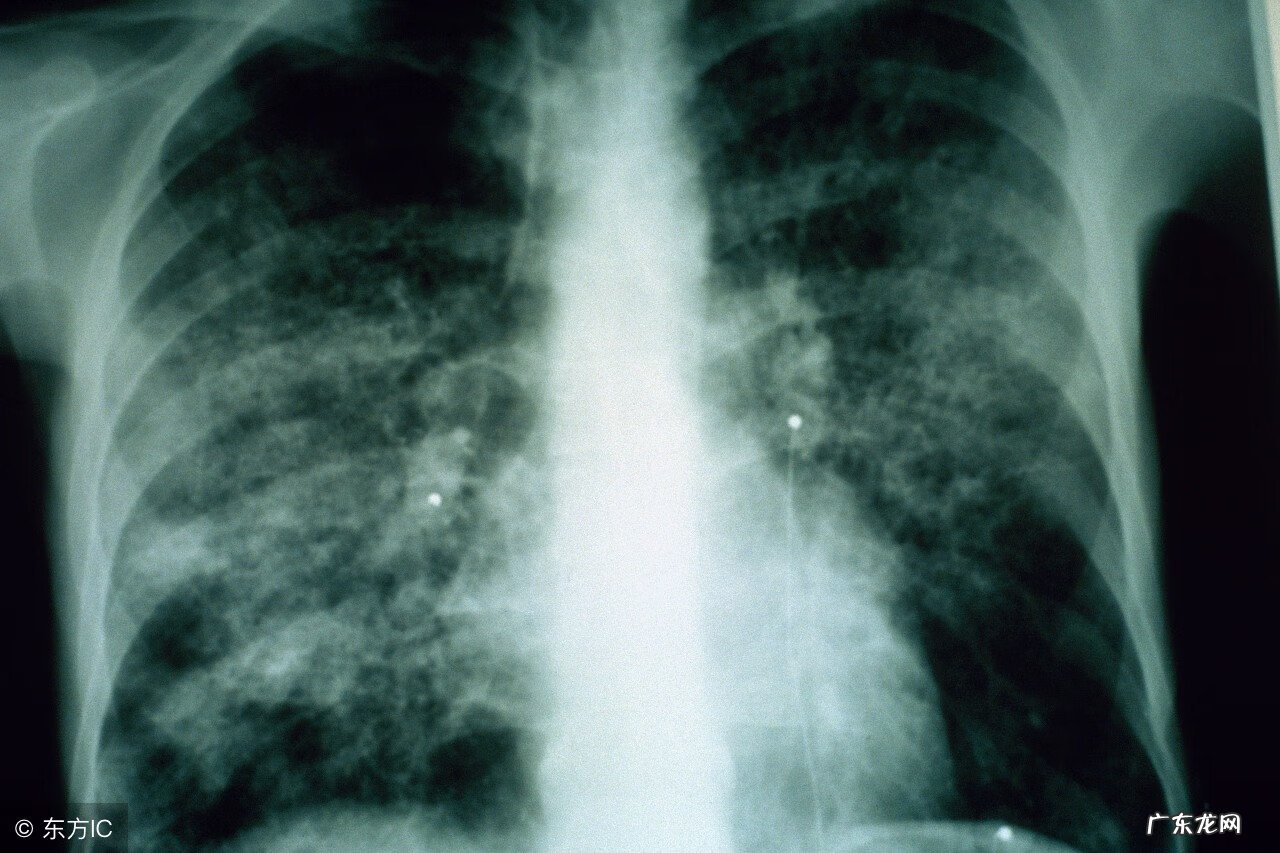

辅助检查方面主要是血清学检查及X线影像学检查 。采集间隔2-4周急性期及恢复期的双份血清标本,不同医院可能采用不同的检测方法,一般恢复期抗体滴度有四倍增高,可确诊 。X线检查显示肺部多种形态的浸润影,呈阶段性分布,以肺下野多见,部分患者可出现少量胸腔积液 。